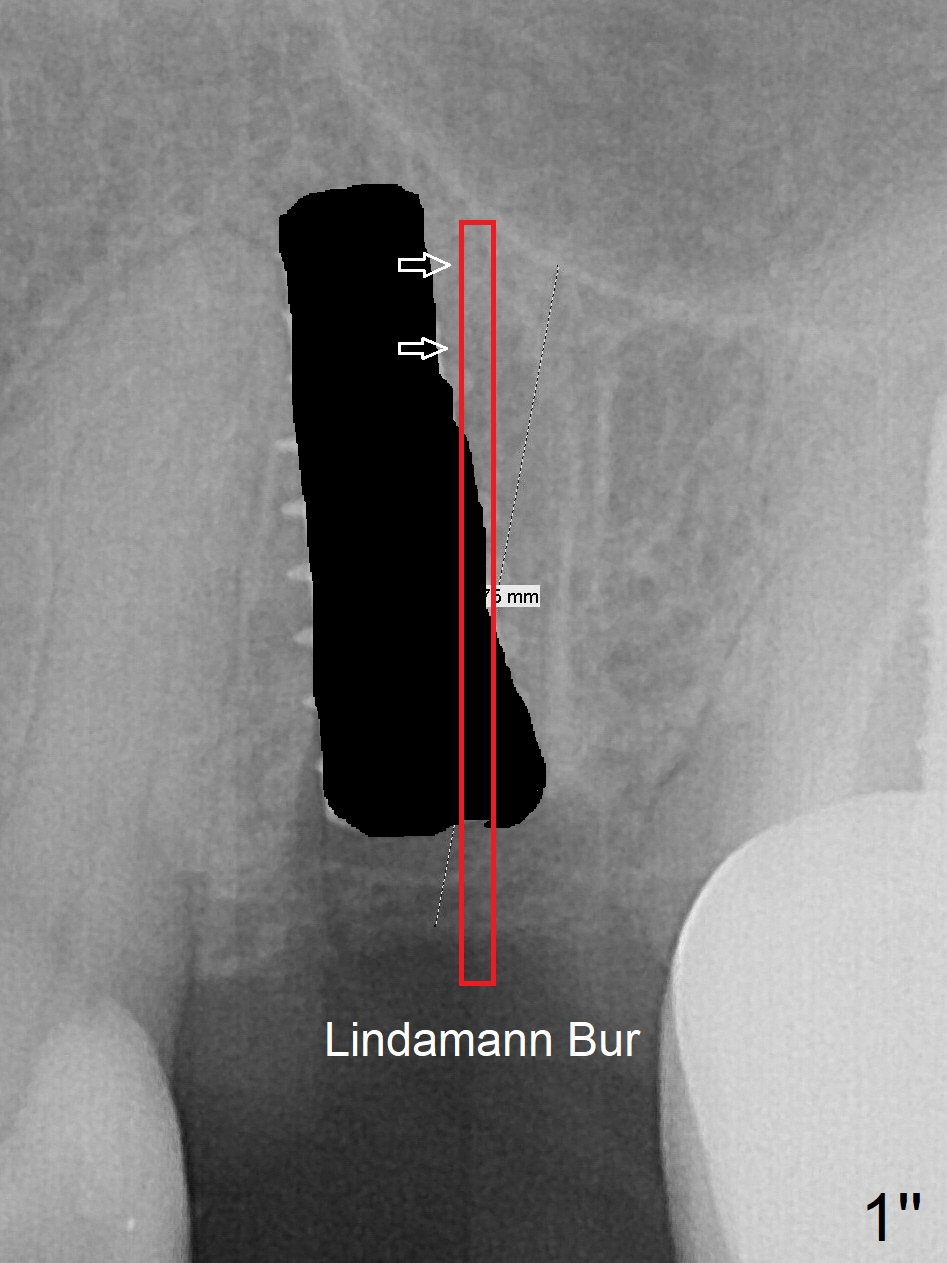

Since the apical native bone is limited at #13 after extraction, no PA is taken until a 4x11 mm dummy implant is placed after 1.6 mm and 3.3 mm drills for 13 mm (Fig.1). The trajectory needs to be changed.

First, the implant is removed (Fig1'). Move the osteotomy distal by using Lindamann bur (Fig.1''). Remove the Lindamann bur (Fig.1'''). Reuse 3.3 m Magic Drill (Fig.1''''). After using Lindamann bur to move the osteotomy distal and reusing 3.3 mm drill, the trajectory of a 4.5x11 mm IBS dummy implant improves (Fig.2 with low stability).